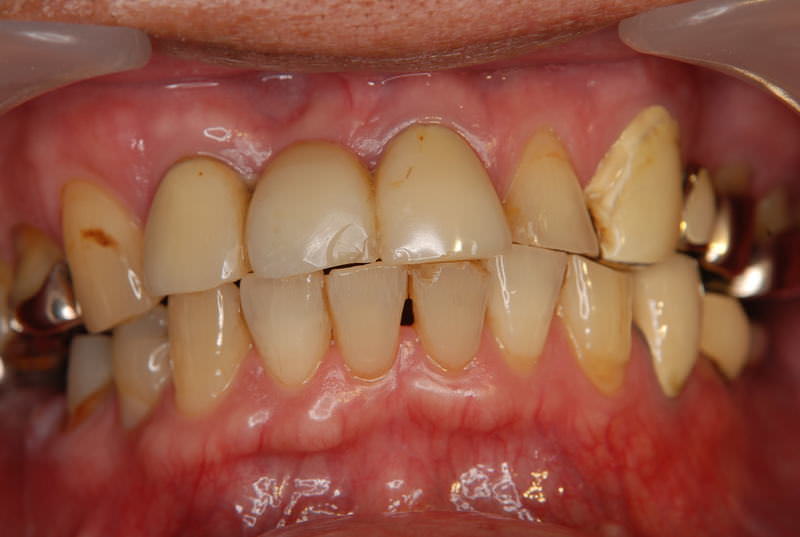

症例360歳 男性 主訴 前歯部がグラグラする

治療前

治療後(5年経過)

※説明

主訴 前歯部の動揺を訴え来院。長いブリッジが装着されており、力学的に荷重負担現象が見受けられる為に、欠損補綴の第一選択肢であるインプラントを選択。インプラント埋入と同時に即時荷重非接触型の仮歯を装着。

約3ヶ月間の免荷期間を経て、ジルコニアブリッジを装着。

リスクとしては、外科的侵襲がある。デメリットは、保険外診療の為、経済負担がある。

費用 126万(税込) (オペ・仮歯・最終補綴物まで含む)